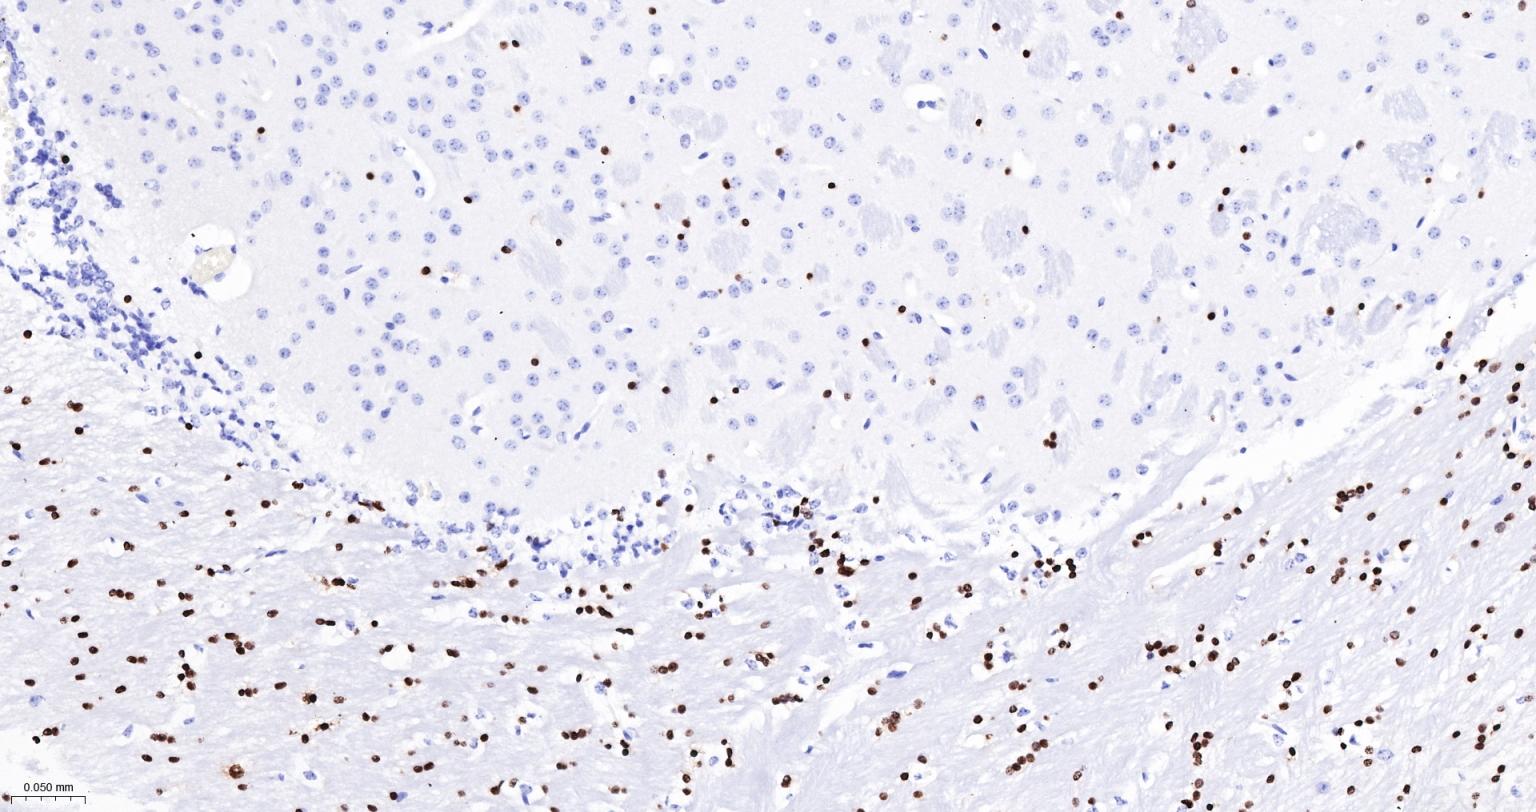

Paraformaldehyde-fixed, paraffin embedded Mouse Cerebellum; Antigen retrieval by boiling in sodium citrate buffer (pH6.0) for 15 min; The section was incubated with OLIG2 Monoclonal Antibody, Unconjugated (bsm-61115R) at 1:200 overnight at 4°C, followed by conjugation to the bs-0295G-HRP and DAB (C-0010) staining.

Paraformaldehyde-fixed, paraffin embedded Human Glioma; Antigen retrieval by boiling in sodium citrate buffer (pH6.0) for 15 min; Antibody incubation with OLIG2 Monoclonal Antibody, Unconjugated(bsm-61115R) at 1:200 overnight at 4°C, followed by conjugation to the bs-0295G-HRP and DAB (C-0010) staining.

Paraformaldehyde-fixed, paraffin embedded Rat Cerebellum; Antigen retrieval by boiling in sodium citrate buffer (pH6.0) for 15 min; Antibody incubation with OLIG2 Monoclonal Antibody, Unconjugated(bsm-61115R) at 1:200 overnight at 4°C, followed by conjugation to the bs-0295G-HRP and DAB (C-0010) staining.

Paraformaldehyde-fixed, paraffin embedded Human Cerebrum; Antigen retrieval by boiling in sodium citrate buffer (pH6.0) for 15 min; Antibody incubation with OLIG2 Monoclonal Antibody, Unconjugated(bsm-61115R) at 1:200 overnight at 4°C, followed by conjugation to the bs-0295G-HRP and DAB (C-0010) staining.

Paraformaldehyde-fixed, paraffin embedded Rat Cerebrum; Antigen retrieval by boiling in sodium citrate buffer (pH6.0) for 15 min; Antibody incubation with OLIG2 Monoclonal Antibody, Unconjugated(bsm-61115R) at 1:200 overnight at 4°C, followed by conjugation to the bs-0295G-HRP and DAB (C-0010) staining.

Paraformaldehyde-fixed, paraffin embedded Mouse Cerebrum; Antigen retrieval by boiling in sodium citrate buffer (pH6.0) for 15 min; Antibody incubation with OLIG2 Monoclonal Antibody, Unconjugated(bsm-61115R) at 1:200 overnight at 4°C, followed by conjugation to the bs-0295G-HRP and DAB (C-0010) staining.

Paraformaldehyde-fixed, paraffin embedded Human Cerebellum; Antigen retrieval by boiling in sodium citrate buffer (pH6.0) for 15 min; The section was incubated with OLIG2 Monoclonal Antibody, Unconjugated (bsm-61115R) at 1:200 overnight at 4°C, followed by conjugation to the bs-0295G-HRP and DAB (C-0010) staining.

(Negative control)Paraformaldehyde-fixed, paraffin embedded Human Colon Cancer; Antigen retrieval by boiling in sodium citrate buffer (pH6.0) for 15 min; The section was incubated with OLIG2 Monoclonal Antibody, Unconjugated (bsm-61115R) at 1:200 overnight at 4°C, followed by conjugation to the bs-0295G-HRP and DAB (C-0010) staining.